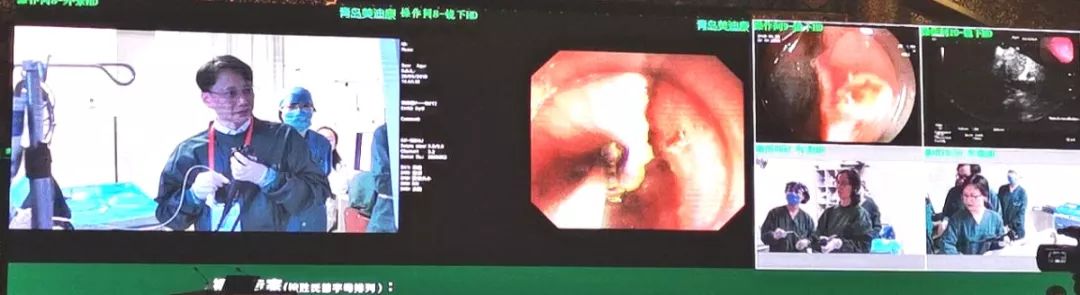

近日,由中华医学会消化内镜学分会主办、北京市医学会和北京协和医院承办2019年北京协和消化疾病及消化内镜国际论坛在北京举行,我院消化内镜中心主任梁玮主任医师应邀进行现场手术演示。此次梁玮主任医师再次通过自创的自牵引技术Q-ESD法,成功施行高难度的食管早癌病灶内镜下粘膜下剥离术,流畅的操作、美观的手术创面,赢得国内外同道们的阵阵喝彩。

与北京协和医院全面合作共建以来,我院各学科积极与北协和相应学科开展深入互动,双方推出了多种形式的人才培养、科研学术合作等,对提升我院学科建设水平和影响力起到了极大的推动作用。受益于此,我院消化内镜中心梁玮主任医师已连续3年应邀在北京协和医院进行早期食管癌内镜切除术演示,展示了学科建设成果。